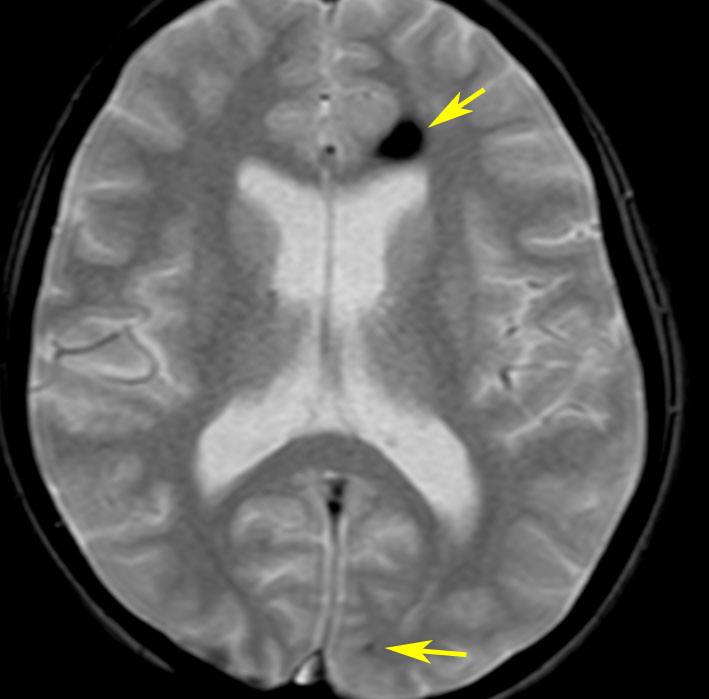

髄芽腫に対する脳脊髄照射36グレイ,8年後のMRI画像です。右前頭葉にごく小さな出血がみられます。その周囲に黒くにじむようなヘモジデリン(鉄)の沈着があります。よく見ると大脳の数カ所に同じような所見がありました。これは脳照射後の微小な静脈の閉塞に起因する血管からの微小な血液漏出 blood cell leakageです。症状を出すこともなく心配ありません。放射線治療後多発性海綿状血管腫と表現されることもあります。